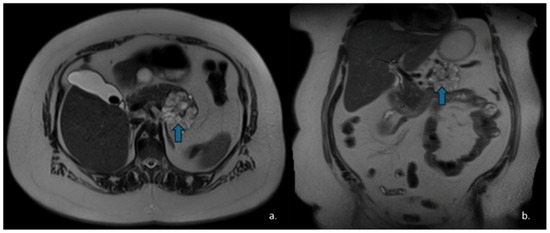

Pancreatic Cystic Lesions: From Basic Knowledge to Recent Guidelines

Pancreatic cystic lesions (PCLs) are increasingly detected due to widespread use of cross-sectional imaging. They encompass a heterogeneous group of lesions, ranging from benign pseudocysts and serous cystic neoplasms (SCNs) to premalignant mucinous cystic neoplasms (MCNs) and intraductal papillary mucinous neoplasms (IPMNs), as [...] Read more.

Pancreatic cystic lesions (PCLs) are increasingly detected due to widespread use of cross-sectional imaging. They encompass a heterogeneous group of lesions, ranging from benign pseudocysts and serous cystic neoplasms (SCNs) to premalignant mucinous cystic neoplasms (MCNs) and intraductal papillary mucinous neoplasms (IPMNs), as well as rare malignant entities such as solid pseudopapillary epithelial neoplasm (SPENs) and cystic pancreatic neuroendocrine tumors (cystic PanNETs). Management of PCLs depends on their malignant potential; therefore, an accurate classification is essential for optimizing treatment. This narrative review summarizes current knowledge on the epidemiology, imaging characteristics, diagnosis, and management of PCLs, highlighting the role of CT, MRI, MRCP, and endoscopic ultrasound. Recent advances in radiomics for lesion characterization and risk stratification, particularly in IPMNs, are discussed. Full article

Show Figures

Figure 1